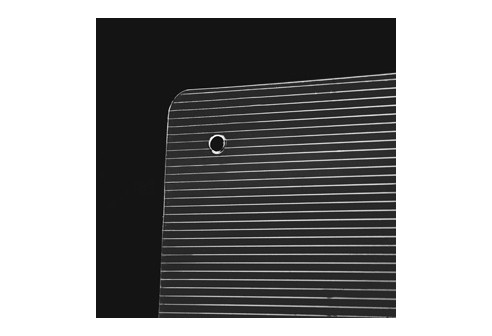

Feuilles de prismes - 3 cm/m

- Additifs prismatique pour le traitement du strabisme - Diamètre utile: 58 mm Attention: Durée maximale de conservation des feuilles: 1 an. Les feuilles ne peuvent être marquées qu’avec des crayons gras ou de cire. Veuillez respecter les instructions de nettoyage.